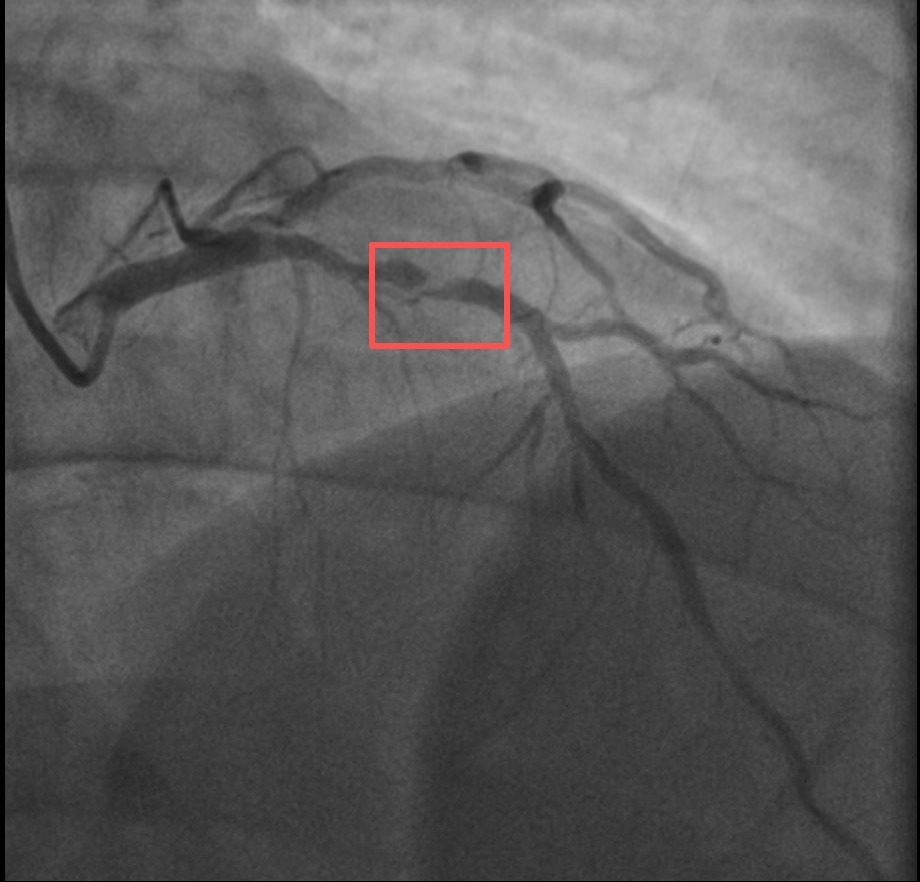

近期,他带孩子到羽毛球场操练,手痒之下亲自上场挥杆仅10分钟左右,就因心前区剧烈绞痛被送进了急诊。浙江医院心血管内科副主任汤益民主任医师分析,剧烈运动导致这位患者心脏的不稳定斑块破裂,进而造成前降支近段次全闭塞。所幸送医及时,接受汤益民团队的紧急介入治疗后,孙先生的身体险情被成功化解。

介入治疗前后影像图